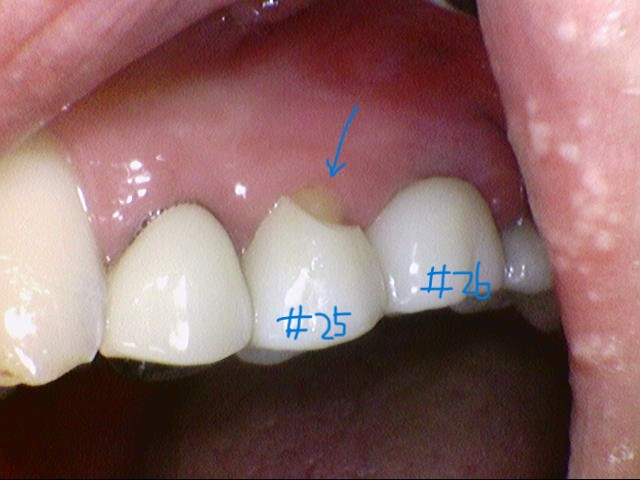

예를 들어, 오래전에 치료한 브리지가 부러졌다며 내원한 환자가 있었다.

#26, 27 사이 화살표 부위가 수평으로 깨져서 이미 분리되어 있었다.

#25 치아의 볼 쪽 화살표 부위 도재가 깨져있다.